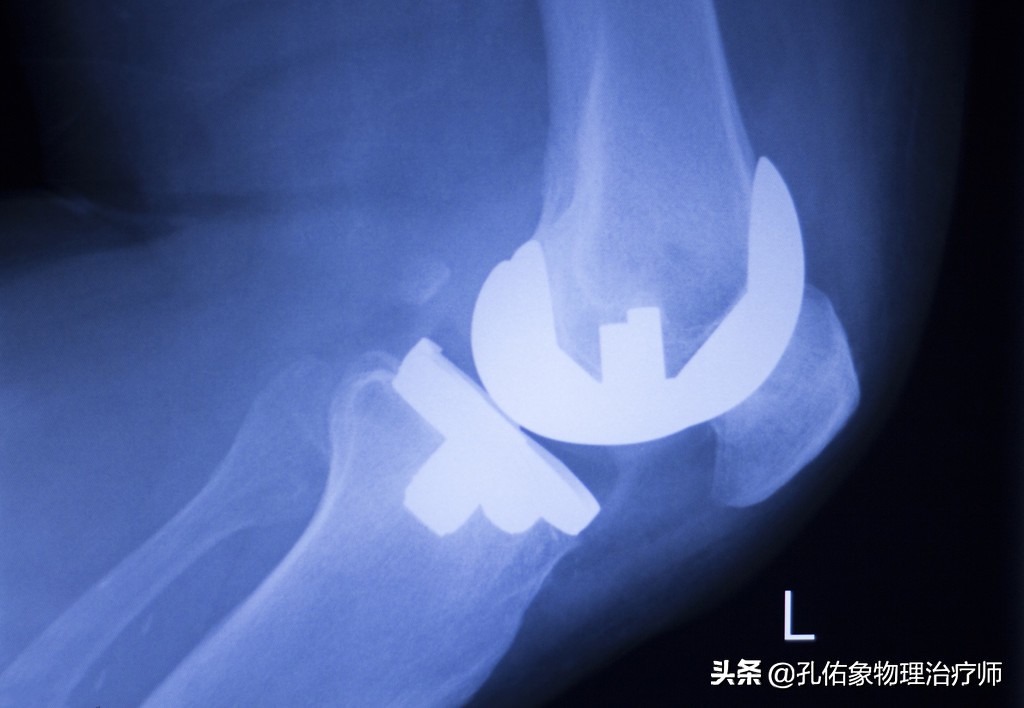

1.避免手术

膝痛在早期时,往往只体现出局部的疼痛,局部的炎症肿胀;但是随着自身的不关注,慢慢的力学改变,膝盖骨与大腿骨撞击就会引起膝盖骨下面的软骨损伤,逐年累月的血液循环障碍、骨质增生、骨赘形成;到这个时候要解决问题,只有通过手术,关节镜下处理或是直接用一个假的膝关节换进去。

我们往往通过以上四个特殊检查就可以发现膝痛是不是膝盖骨的软骨软化所致?当然了,也可以去拍一张膝关节的正侧位片看看,一般早期疼痛往往在片子上也看不出啥问题,此时需要拍特殊体位的。

- 拍X片(轴位片)

一般在医院里边,很多医生也不会让患者去拍轴位片,都喜欢去拍正侧位片。但是针对膝痛早期的人而言,在下蹲过程中出现疼痛时的角度去拍轴位片,会发觉挺有意思的,膝盖骨是外移的,并没有在正常的髁间窝里边,这就是典型的膝盖骨软骨软化的表现。

这样的膝痛,在早期通过片子是很难发现的,所以你无论是做啥治疗,效果都不好。只有找到病因后,从根本的力学入手治疗才是上策。若是不及时治疗,使膝盖骨一直处于不正确的轨迹里面运动,最终膝痛厉害,活动受限,拍X正侧位片会显示膝盖骨边缘骨质增生、骨硬化改变及粗糙不平,膝盖骨关节间隙狭窄。